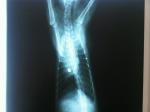

-Tranquila, ya sabes que con las capas que damos no hay problema. Bueno, le daremos una extra para reforzar. Fíjate, ni gota de grasa en el abdomen, todo se maneja estupendamente. Aquí está el ovario izquierdo.

-Pues que está algo activo, yo creo que estaba a punto de tener el celo. Hemos hecho bien, si no lo hacemos ya hubiéramos tenido que esperar 3 ó 4 meses.

-El derecho está tranquilo, ahora voy a por él. Ligo el pedículo ovárico y corto por encima. Ya está. Voy al derecho.

-Ya sabes que aquí no hay que correr. Vamos fenomenal de tiempo, solo me queda ligar el cuello uterino y luego a cerrar. No hay prisa.

-Estupendo, ya está todo. Qué fácil ha sido. Pásame la sutura para el peritoneo y la aponeurosis interna.

-Gracias. Patrón continuo, luego uno de reinversión, a continuación el subcutáneo y para acabar la piel.

-El subcutáneo y la piel. En 5 minutos acabamos.